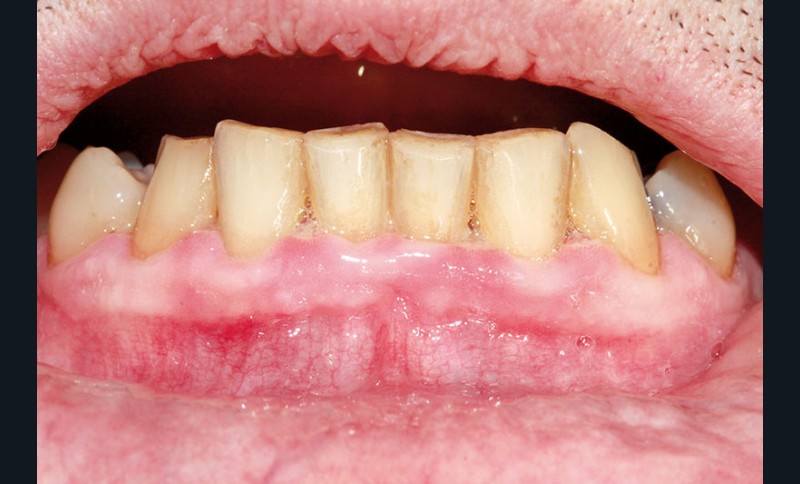

• en endo-buccal, la présence d’une inflammation gingivale sévère notamment au niveau des secteurs antérieurs, caractérisée par des papilles ulcéronécrotiques et hémorragiques au contact, associée à une adénopathie sous mandibulaire droite douloureuse à la palpation.